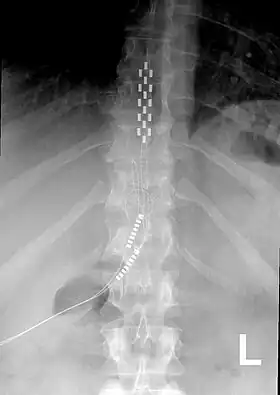

Chronic pain

Neurostimulation for chronic pain is primarily through the use of spinal cord stimulators.[11] These devices deliver electrical stimulation to different areas of the spine based on where they are implanted. Since 2012, Medtronic has produced spinal cord stimulators with accelerometers that can predict the patient's position. The device can be programmed to give additional electrical stimulation if the patient is thought to be in a more painful position.[12]